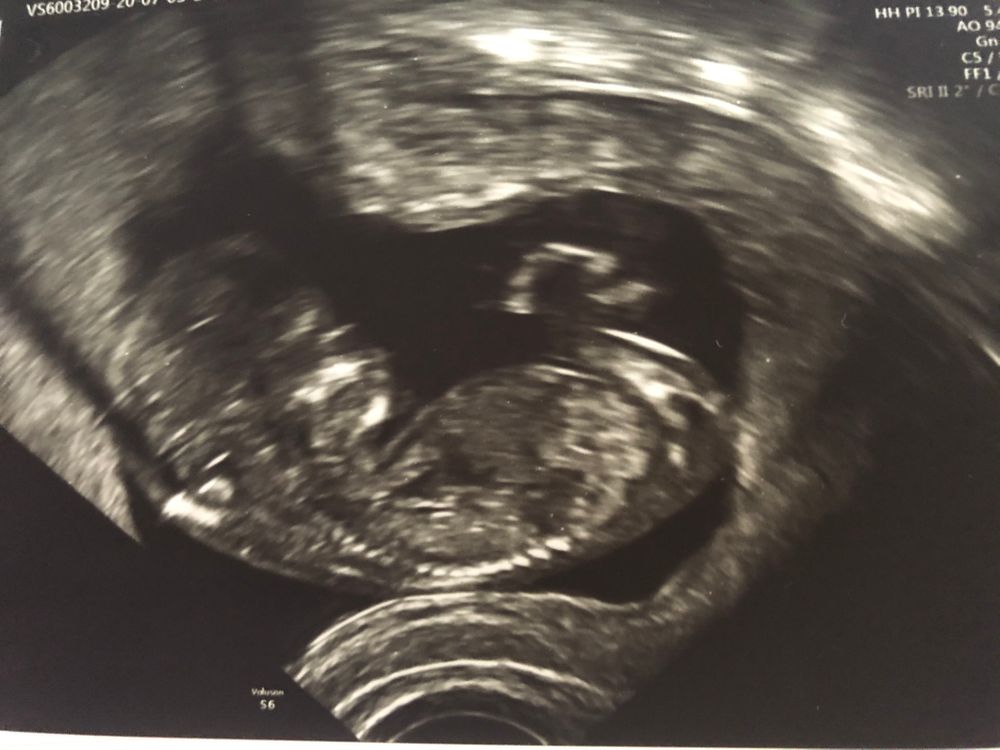

Первый скрининг❤️

сегодня был первый скрининг в 12,1. И все у нас просто отлично, сказали, что красивый носик 😂

Малышка 6 см, сроку соответствуем, я ужасно счастлива, сегодня наконец-то рассказываем родителям 😍😍😍